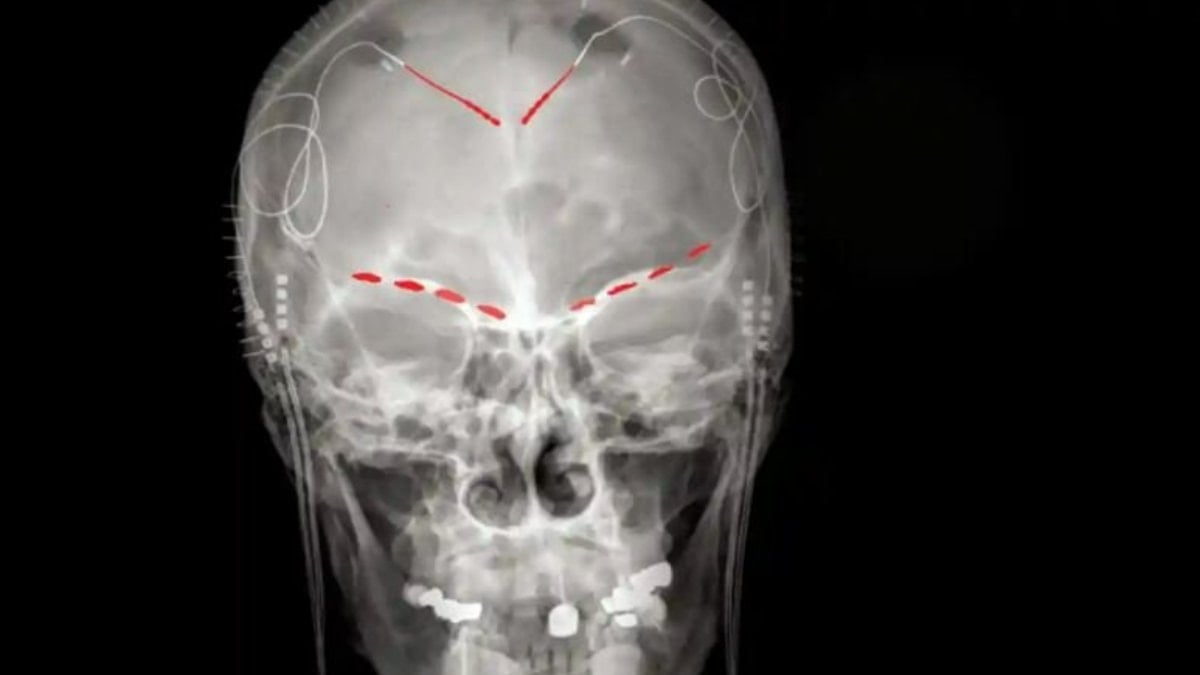

Araştırma: Beyindeki kronik ağrıyı tespit edebilen algoritma geliştirildi

Hastalardaki kronik ağrının altında yatan beyin aktivitesini birinci defa çözen yeni bir araştırma, acı çeken…